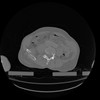

34 CUERPO,CE,Vol,1.0,CUERPO,,